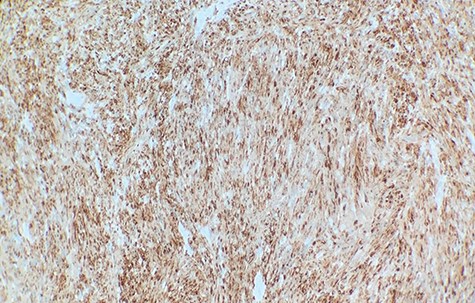

Macroscopically, the tumor appeared encapsulated, rubbery and pink-tan in color. Microscopic examination reveals that tumor composed of biphasic spindle hypercellular Antoni A areas and hypocellular Antoni B areas (Fig. 1). Higher magnification reveals that spindle tumor cells are narrow, elongate, wavy with tapered ends interspersed with collagen fibers (Fig. 2). Immunohistochemical staining revealed that most tumor cells reacted strongly for S-100 protein (Fig. 3). Combined with immunohistochemical profile, these histological features are diagnostic of benign schwannoma. Patient was discharged home on the same day as the operation. At the 1-month follow-up, he was symptom free, without any pain or sensory disturbances.

Immunohistochemical staining revealed that tumor cells are strongly positive for S-100 protein (×40).

Schwannomas are the most common type of peripheral nerve tumors. They can arise from peripheral, spinal or cranial nerves. Though the cause is unknown, multiple schwannomas are known to develop from genetic disorders such as neurofibromatosis type 2, schwannomatosis or Carney complex. Commonly affected areas are the head and flexor surfaces of the upper and lower extremities and the trunk. Because of their slow growth, many patients are asymptomatic for months or years before experiencing symptoms. Typical presenting signs and symptoms of pain, paresthesia or weakness are due to direct nerve invasion, mass effect, involvement of surrounding tissues and disfigurement [1]. Therefore, neurological examinations assessing reflexes, motor and sensory functions are vital. Diagnosing can be difficult due to their slow growth and their mimicry of symptoms causing various diseases. Imaging tests such as computed tomography or X-rays are performed but magnetic resonance imaging (MRI) is the most beneficial imaging modality to aid in the diagnosis of schwannoma. T2-weighted MRI shows schwannomas as well as circumscribed ovoid masses with high intensity signal [2]. Surgical biopsy is the definitive diagnosis. Furthermore, schwannomas have a strong immunoreactivity for S-100 protein. Treatment depends on multiple factors such as the location of the tumor, severity of symptoms and whether it is benign or malignant. Conservative treatment is done for those that are asymptomatic while surgical resection is done to remove symptomatic tumors or those that grow quickly. Radiation can be combined with surgery for malignant schwannomas. Recurrence is unlikely after surgical resection with complete and rapid relief of symptoms.

Diagnostic criteria for schwannoma requires a biphasic cellular pattern, consisting of two distinct regions namely Antoni A and Antoni B. Antoni A is hypercellular with eosinophilic cytoplasm, whereas Antoni B is hypocellular and has loose tissue comprising clear, vacuolated cytoplasm due to lipid accumulation. In addition, nuclear palisading is a typical feature and when pronounced forms Verocay bodies [4].